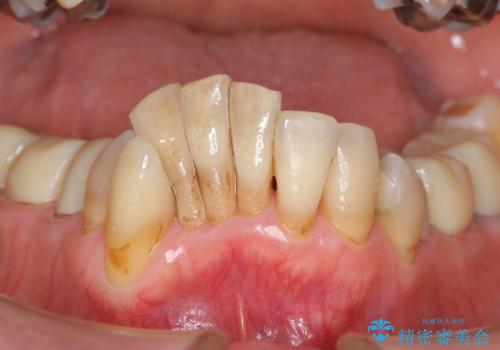

- 上顎前歯の黒ずみの改善、下顎前歯の十度なガタつき、矯正治療とセラミック治療を含む全体的な治療を希望され来院されました。

銀歯を高強度の仮歯に替えたのち、下顎前歯のみの部分矯正→全体的なマウスピース矯正治療(インビザライン)→最終的なセラミック治療と治療を進めます。

矯正治療と目立つ銀歯のやりかえを行ったことでかみあわせだけでなく、審美性・清掃性も改善し口腔内の環境を劇的に改善することができました。